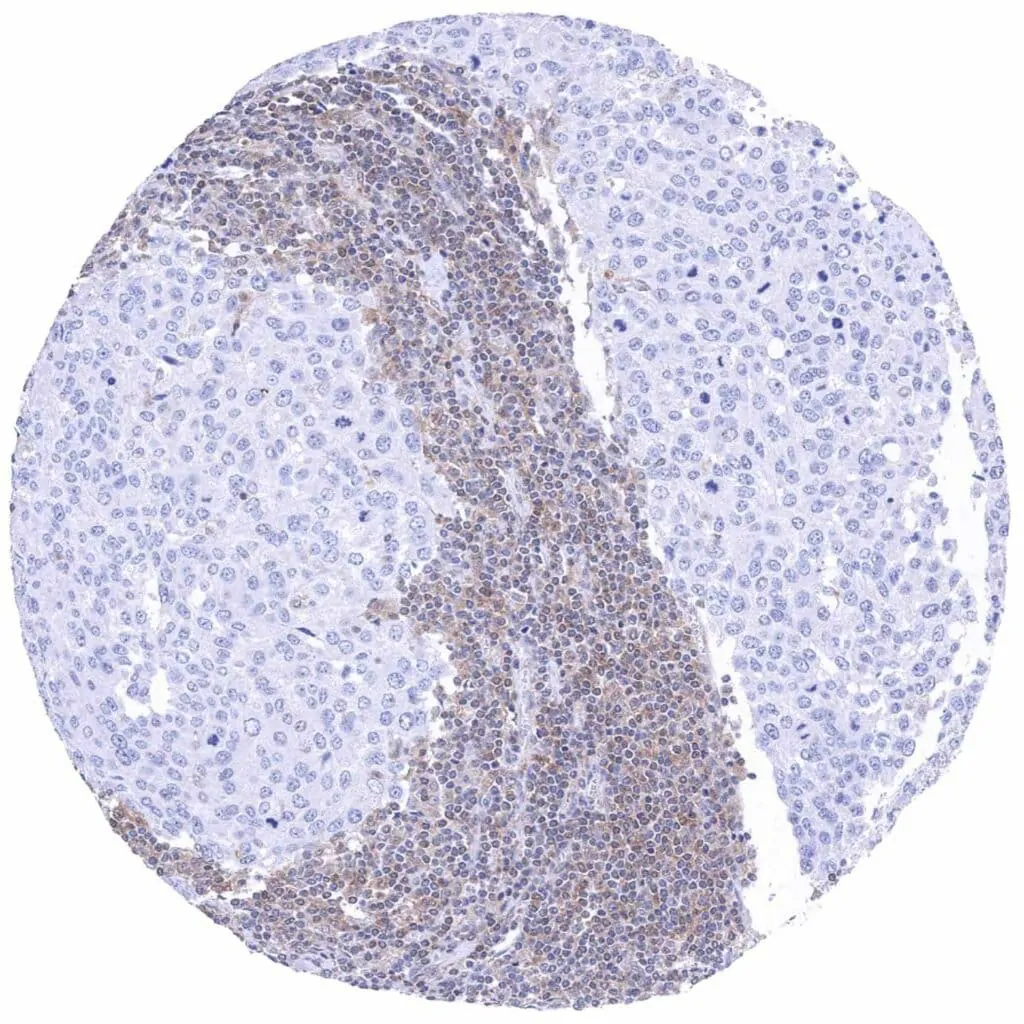

Lymph node – Hodgkin's lymphoma with complete absence of MTAP staining in tumor cells. Intense MTAP staining of associated non-neoplassic cells.